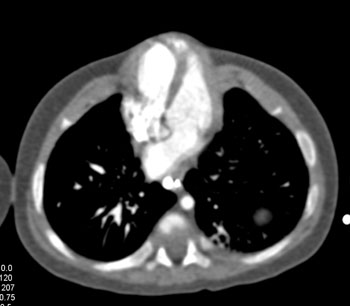

Question 8: Infant with chest and abdominal wall defect. What is the diagnosis?

Diagnosis: Pentalogy of Cantrell

• Exteriorization of the heart

• Associated with CV malformations like ASD (50%), VSD (18%) and TOF (11%)

• Omphalocele and defect lower sternum

• Deficiency of diaphragmatic pericardium

• Prognosis: death within first month of life